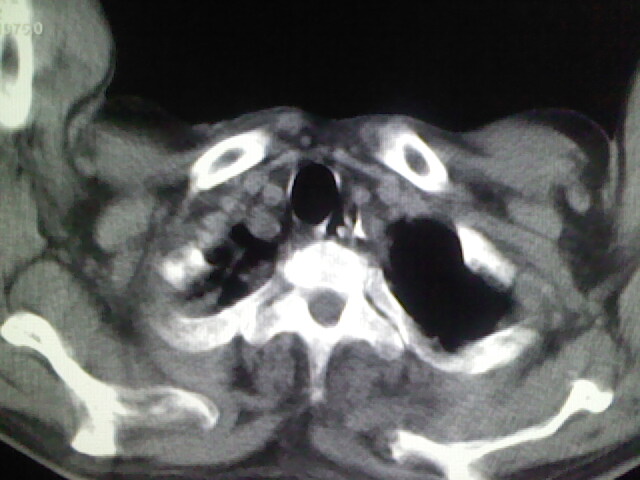

男,70岁,脑出血,长期卧床,左侧背部可触及肿块

食道里是什么

你放上去的